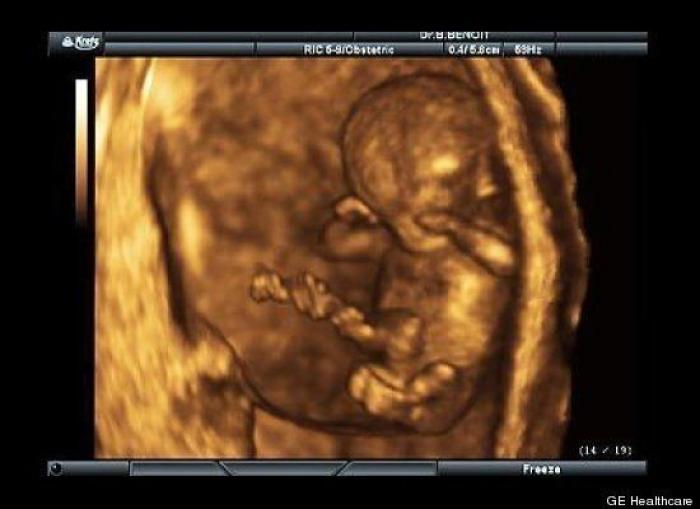

En esta galería puedes ver en fotos como es el desarrollo de un feto de semana en semana:

Desarrollo del feto, en fotos

Ver la galería